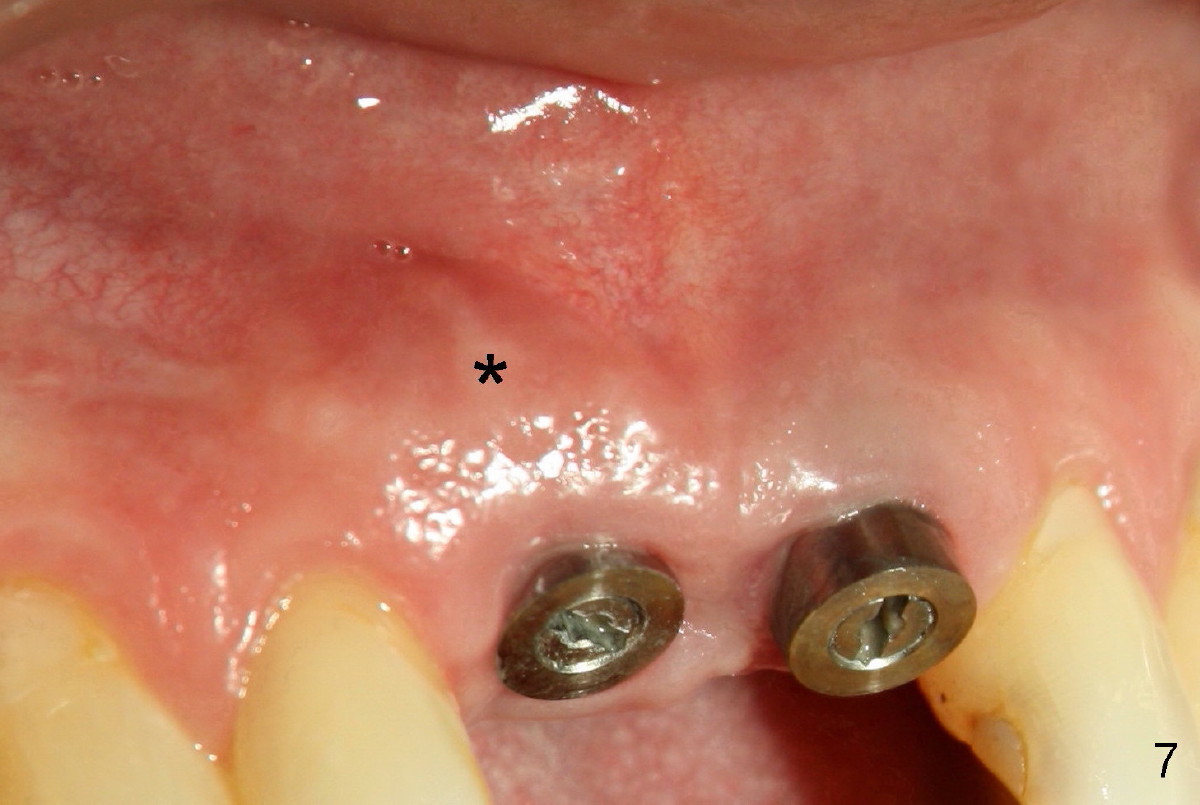

Wounds heal uneventfully. Two months later, an implant is placed at the site of #8 (Fig.5).  Fig.4 is a preop X-ray, showing graft (*).  Two weeks later, swelling and pain recur (Fig.7).  Amoxicillin 500 mg tid is prescribed for a week.  Symptoms and signs improve after antibiotic treatment (Fig.8).  A month later, the patient complains tenderness on touching the implant of #8 without swelling.  A X-ray film is taken (Fig.6).  The symptom is again controlled while taking oral Clindamycin and relapses when treatment is terminated.  What should we do?